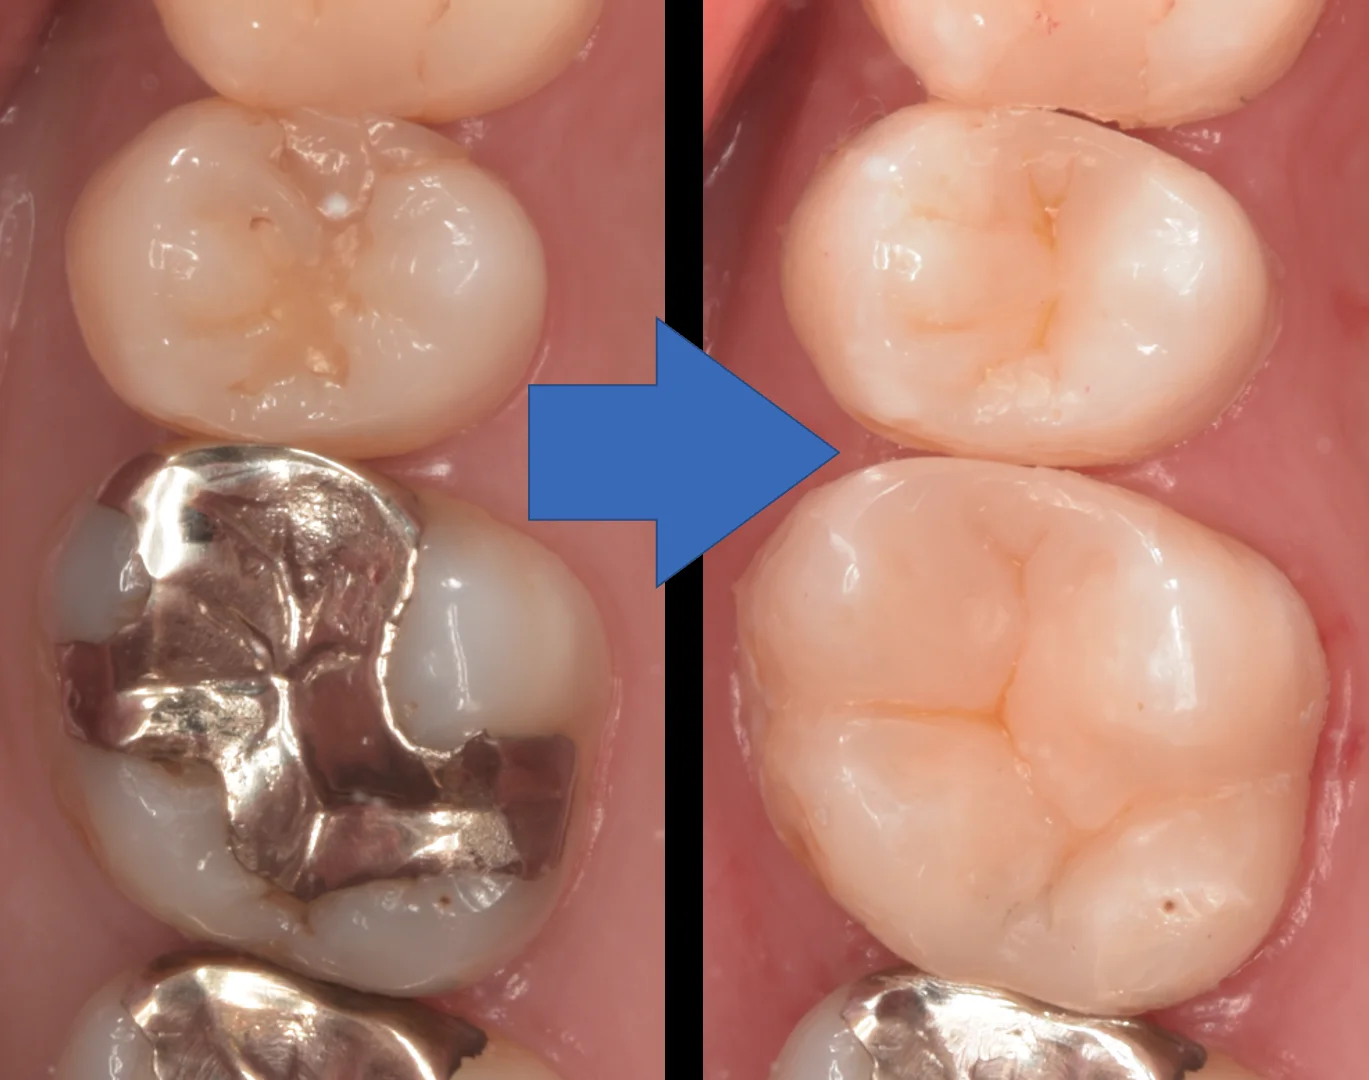

術前術後です。

遠方から長時間の治療、お疲れ様でした!

なるべく長く使えるといいですね!